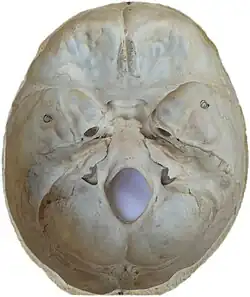

Photo. Base of skull. Superior view.

Photo. Base of skull. Superior view. -